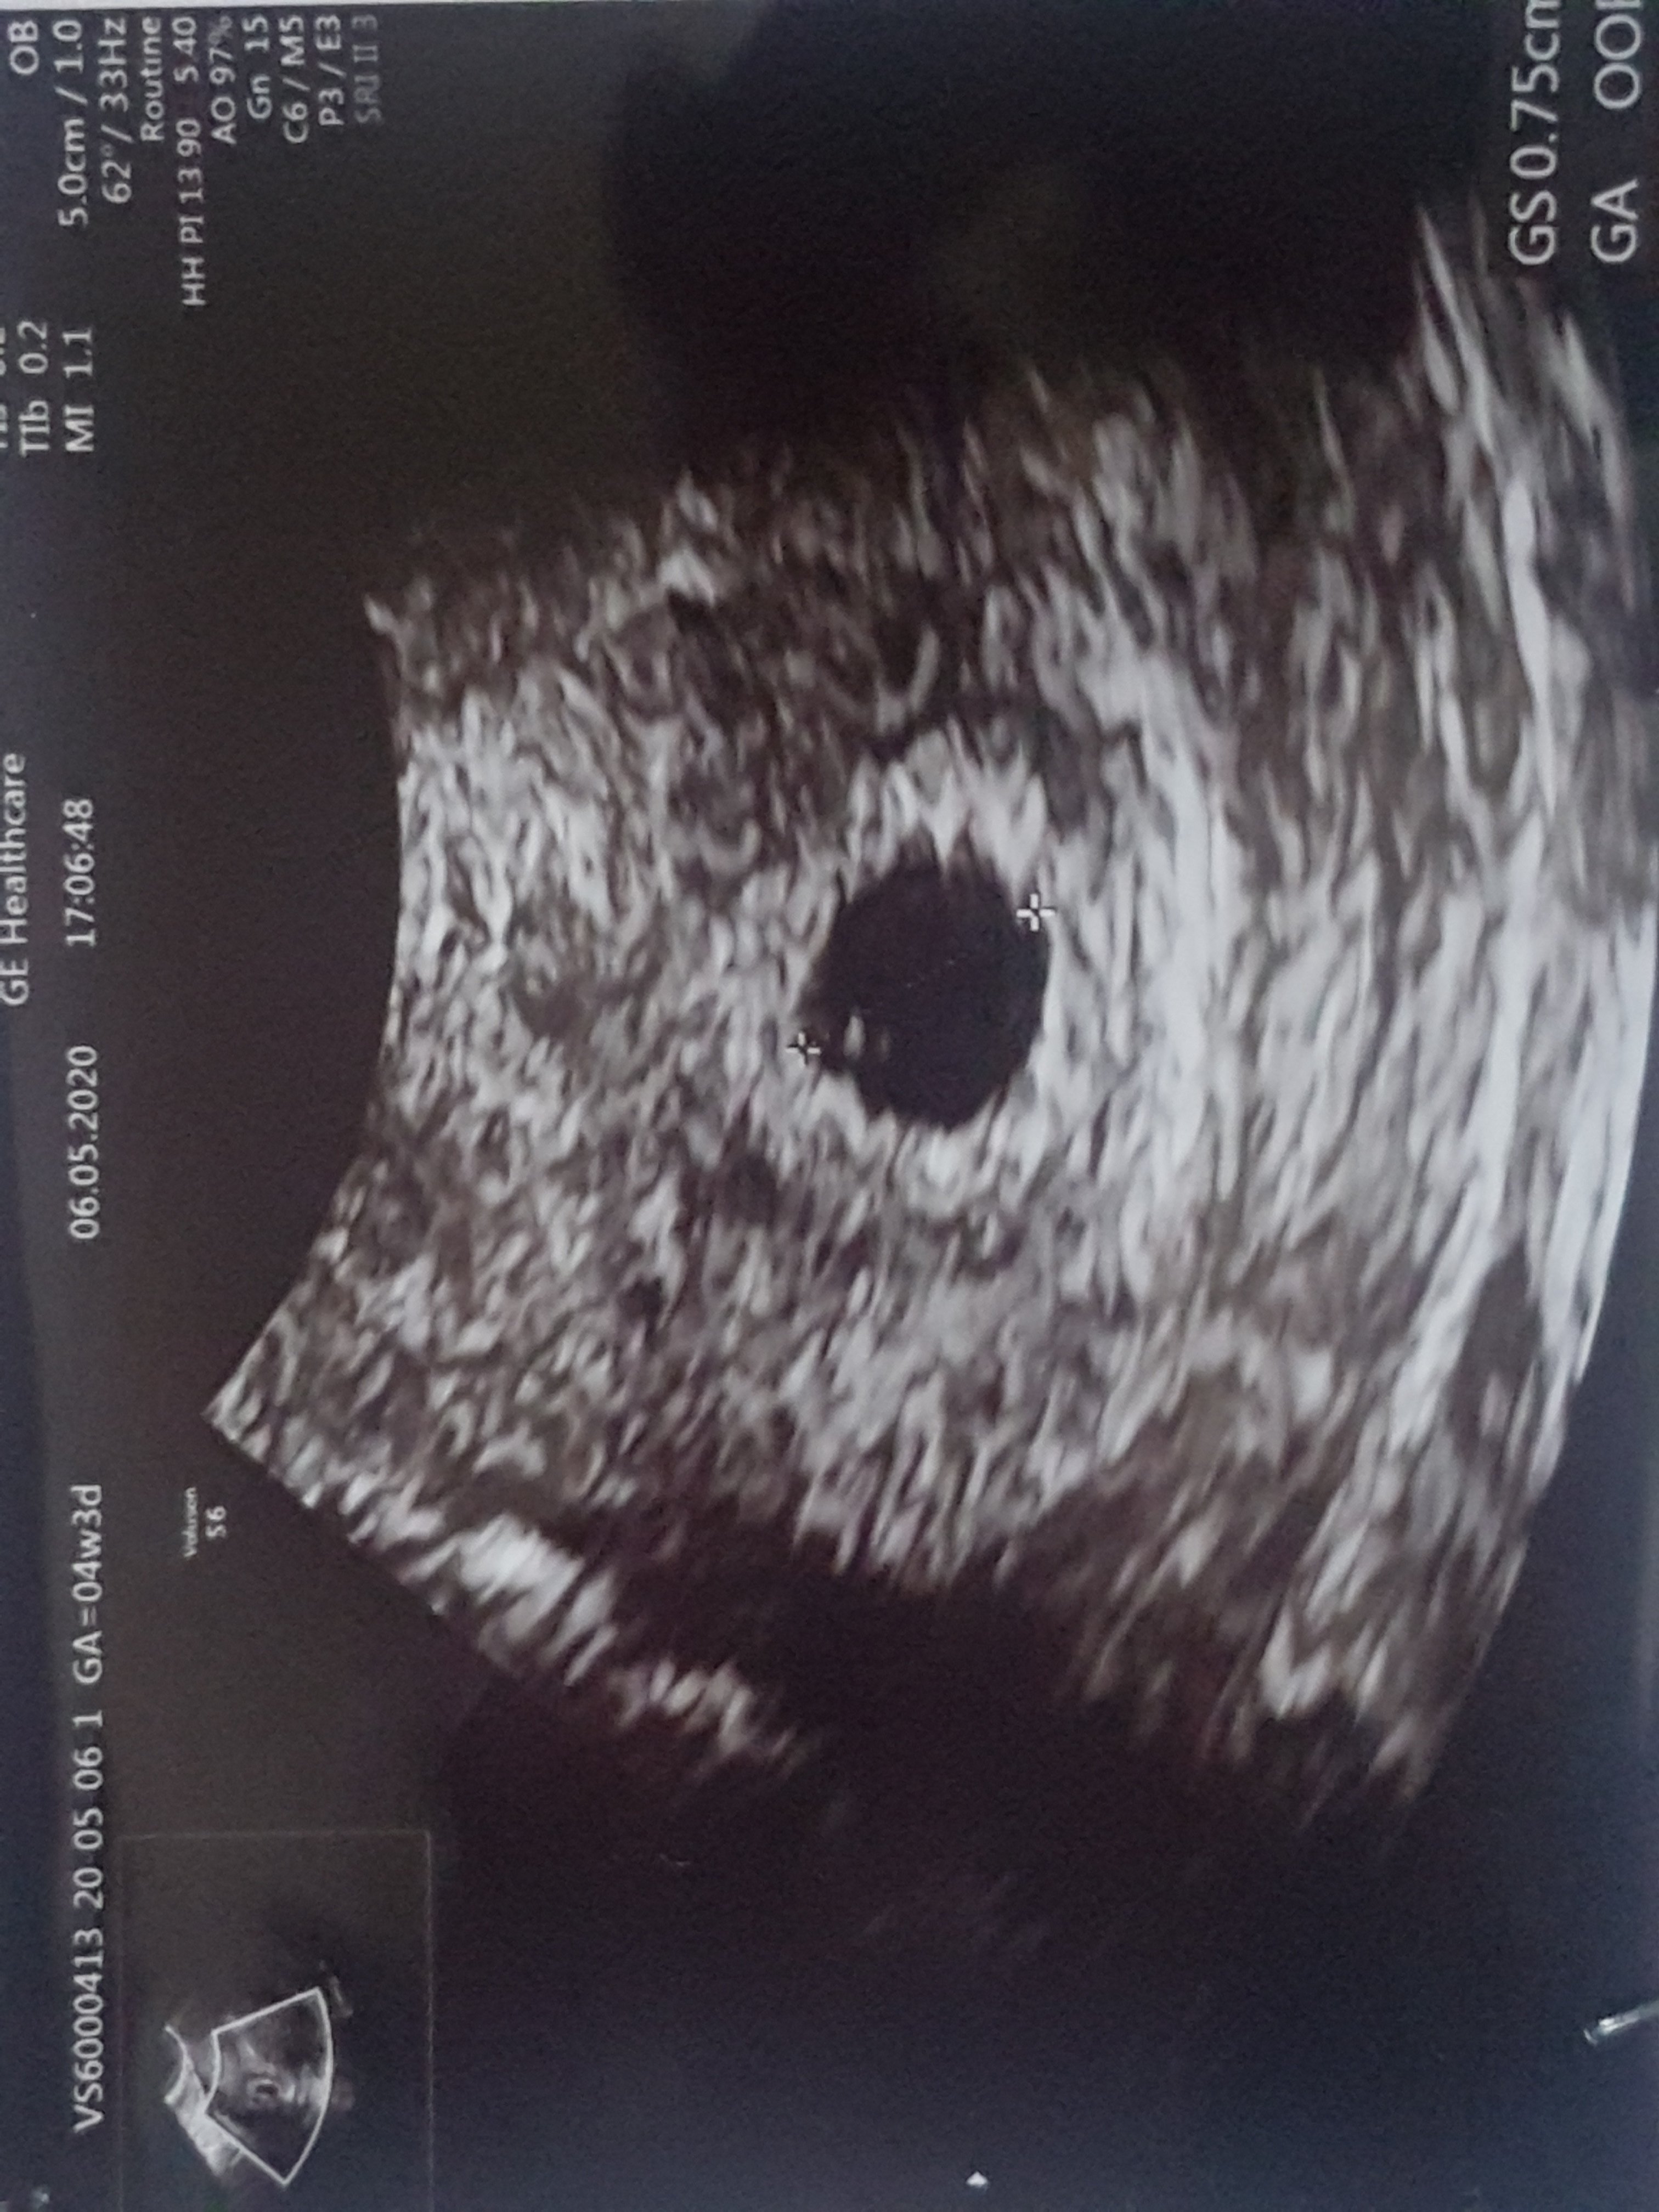

Narazie cieszę się, że pęcherzyk jest w macicy bo tak bolał mnie jajnik myślałam już że może to ciąża pozamaciczna. Na szczęście jest w macicy, ale jeszcze muszę się uzbroić w cierpliwość do pon wtedy teoretycznie powinno być widać zarodek a jak nie to się chyba załamie.Super!!!!!❤❤❤❤